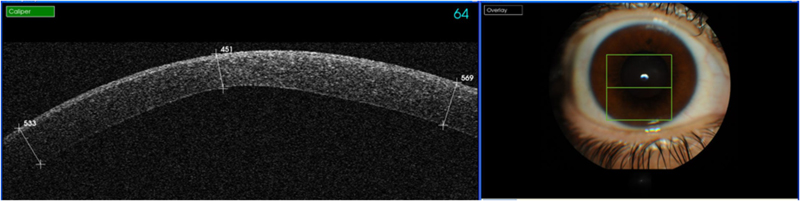

Figura 2), opacidades corneales estromales y su profundidad, patologías asociadas al LASIK (

Figura 3 y

Figura 4, fase infecciosa de una queratitis estromal en la interfase y posterior resolución) y desprendimientos de la membrana Descemet, entre otras muchas patologías.

Figura 3. Infección en operado de LASIK.

Figura 4. Resolución de la infección con aposicionamiento del flap.